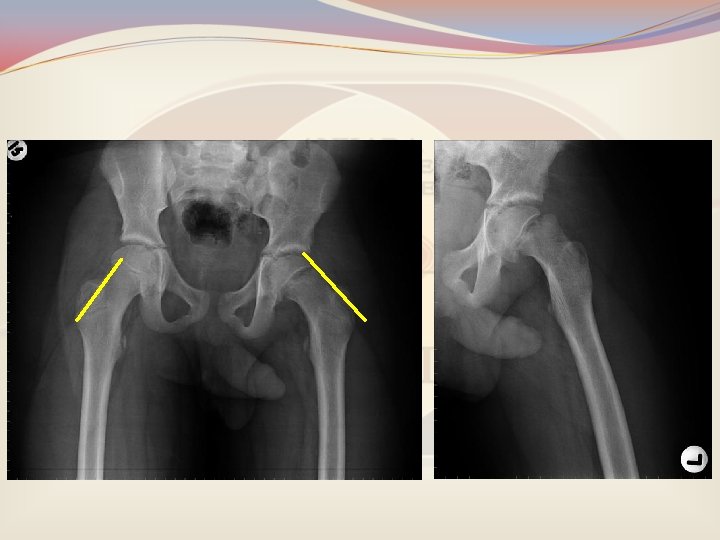

• Adelosan, kilolu erkek, ani başlayan kalça ağrısı • Aksama ve ayak dışa dönük basma • Azalmış kalça fleksiyonu, 1 -2 cm kısalık

Femur Başı Epifiz Kayması • 8 -13/100. 000 • Erkek / Kız oranı 2. 4 • Sol tarafta sık • Olguların % 20 -40' ında iki taraflı tutulum

Neden Kaynaklanır? • Büyümenin en hızlı olduğu 10 -16 yaş grubunda sıktır. • Obezite sık görüldüğünden risk olarak kabul edilir. • 10 yaş ve altında yada 16 yaş üstünde görülürse Hipotiroidi, büyüme hormonu hipogonadizm saptanabilir. bozuklukları,